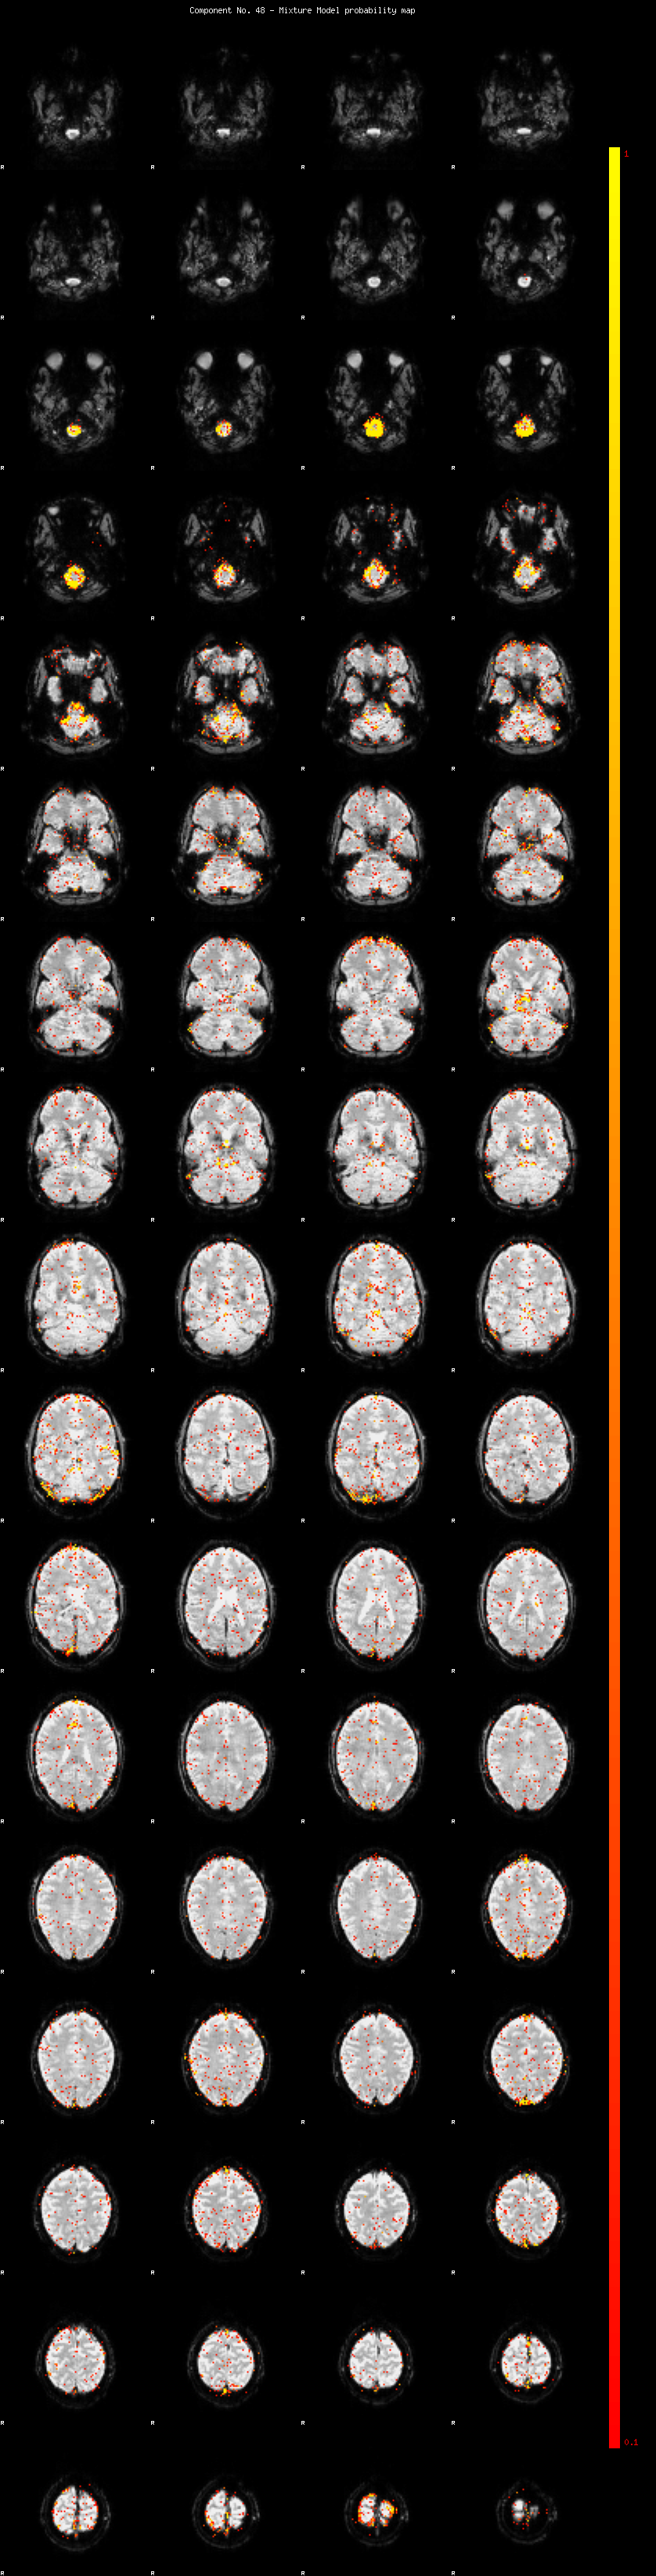

IC_48 Mixture Model fit

Means : -0.000000 2.620656 -2.575280

Vars : 1.000000 2.570731 2.431624

Prop. : 0.965580 0.017733 0.016687